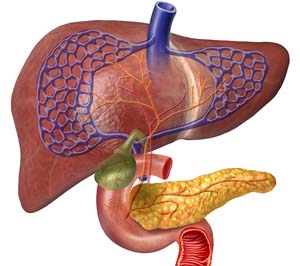

오늘은 췌장암 초기증상 10가지에 대하여서 알아보도록 하겠습니다. 췌장은 명치끝과 배꼽 사이 상복부에 자리잡은 일종의 소화기관으로서 각가지 소화 효소와 인슐린을 분비하여 장내 음식물을 분해하고, 혈당을 제어하는 역할을 담당하죠. 췌장은 십이지장과 연결되어 있어 분비된 소화 효소는 십이지장으로 누설되고 위에서 내려온 음식물들과 섞여요.

췌장은 해부학적으로 두부(머리 부분), 체부(몸통 부분), 미부(꼬리 부분)로 나눠집니다. 두부는 담관(담즙의 배출 통로)과 연결되어 있어 두부에 췌장암이 발생하면 담관이 막히면서 황달이 일어날수 있어요.

미부는 비장과 연결되어 있죠. 소장과 대장 일부에 혈액을 주는 상장간막 동맥은 대동맥으로부터 분지 되어 췌장과 인접해 주행하죠. 췌장에 일어나는 종양은 인슐린 등 호르몬을 분비하는 내분비 세포에서 출현하는 종양(5~10%)과 소화 효소의 분비와 맺어진 외분비 세포에서 소망하는 종양(90% 이상)으로 나눌 수 있죠.